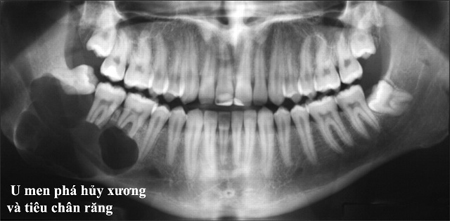

Nang vùng Răng Hàm Mặt